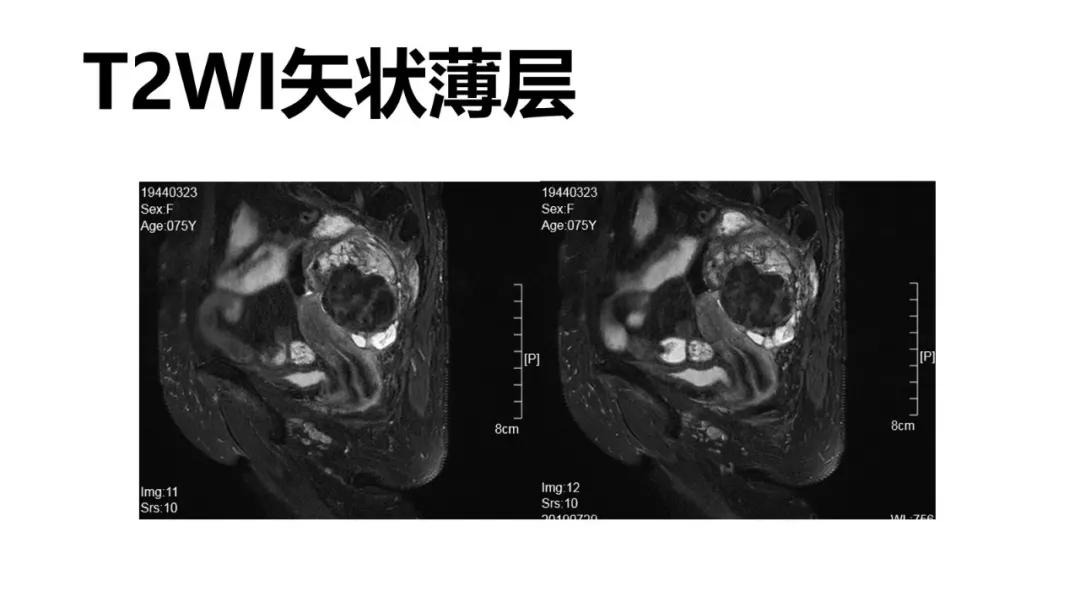

病例10

女,39 岁,体检发现盆腔肿块1月余

CA125:51U/ml

病理:左侧卵巢卵泡膜-纤维瘤